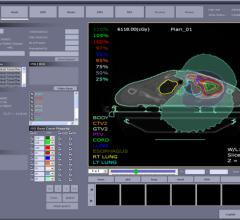

The Koo Foundation Sun Yat-Sen Cancer Center (KF-SYSCC) has established an entirely paperless and filmless clinical process in radiation oncology, designed to enhance patient safety as well as operational efficiency. Using the Aria oncology information system from Varian Medical Systems, the clinical team has automated essential tasks, built in safety-checks and centralized patient information for easier access by staff members.

IBA (Ion Beam Applications S.A.) announced that the first patient case in the United States has successfully been quality controlled using myQA Global QA Platform at the LewisGale Regional Center in Pulaski, Virginia.